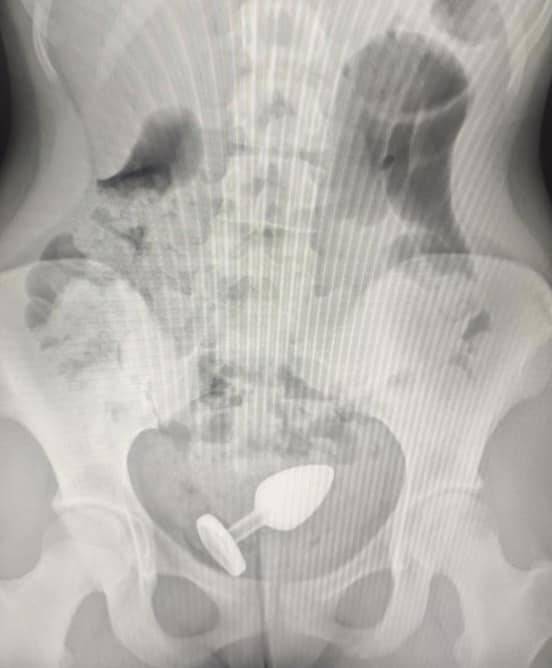

Як зазначають у лікарні “Охматдит”, хірурги та ендоскопісти витягували з пацієнтів флакон з-під парфумів, освіжувач повітря, моркву, вібратор, дезодорант, анальну пробку, ковпачки та вейп, – пишуть “Миколаївські новини”.

Один із останніх таких випадків стався з 16-річним хлопцем, у животі якого лікарі виявили вібратор. Три години вібратор продовжував працювати всередині пацієнта, приводячи до дискомфорту, болю в животі та кровотечі.

Подібні випадки є дуже небезпечними для здоров’я пацієнтів. Сторонні предмети можуть призвести до запалення кишківника, перфорації, сильної кровотечі та перитоніту.

У таких випадках слід негайно звернутися по медичну допомогу до лікарні, а не намагатися допомогти собі самостійно. Чим швидше фахівці приберуть сторонній предмет, тим більше шансів уникнути тяжких наслідків.